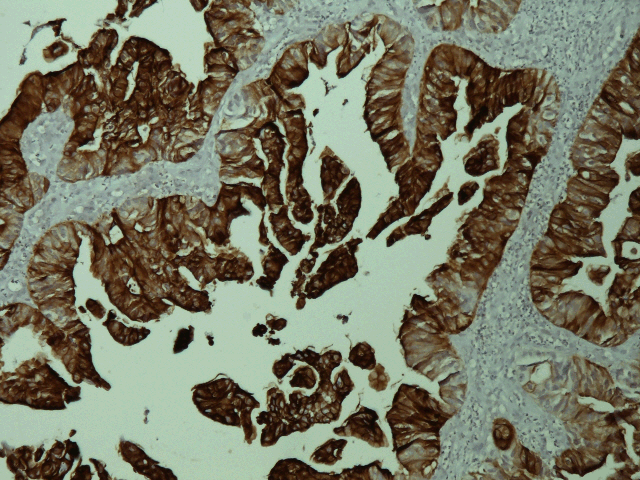

A 46-year-old man presented to us with complaints of swelling and pain in the lower gingiva. Examination of the oral cavity revealed a deep red and hemorrhagic mass that extend from tooth 27 to tooth 32 (figure 1). Medical history was remarkable for rectal adenocarcinoma for which he had undergone abdominoperineal resection one year earlier (T3N1M0), without any adjuvant treatment. The serum CEA and CA19-9 levels were 44 IU/ml and 19 IU/ml, respectively. A head-neck CT scan showed a 3.6 x 1.5 cm soft tissue mass on the right mandible with involvement of the underlying bone. Pathological examination by biopsy of the gingival tumor revealed moderately differentiated adenocarcinoma. Immunohistochemical (IHC) staining showed negativity for cytokeratin 7 and positivity for cytokeratin 20 (figures 2, 3). The gingival lesion was considered as the metastasis from the rectal cancer. A complete workup revealed liver and lung metastases.

Figure 3: Immunohistochemical staining positive for cytokeratin 20.